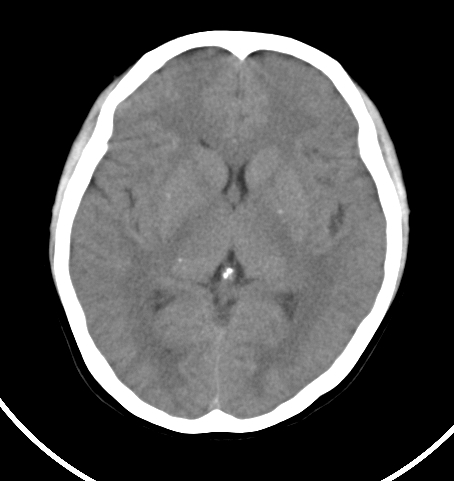

病人女 35岁 自述头晕 头痛

双侧基底节区及右侧丘脑区多发点状钙化,周围未见水肿及占位征象.余未见明显异常.考虑:脑囊虫病<囊虫的退变或死亡期>请结合有无相关病史.

以下是引用苯小孩在2007-4-20 15:47:00的发言:[br]双侧基底节区及右侧丘脑区多发点状钙化,周围未见水肿及占位征象.余未见明显异常.考虑:脑囊虫病<囊虫的退变或死亡期>请结合有无相关病史.

支持.

颅内有散在钙化

脑囊虫病理性钙化。